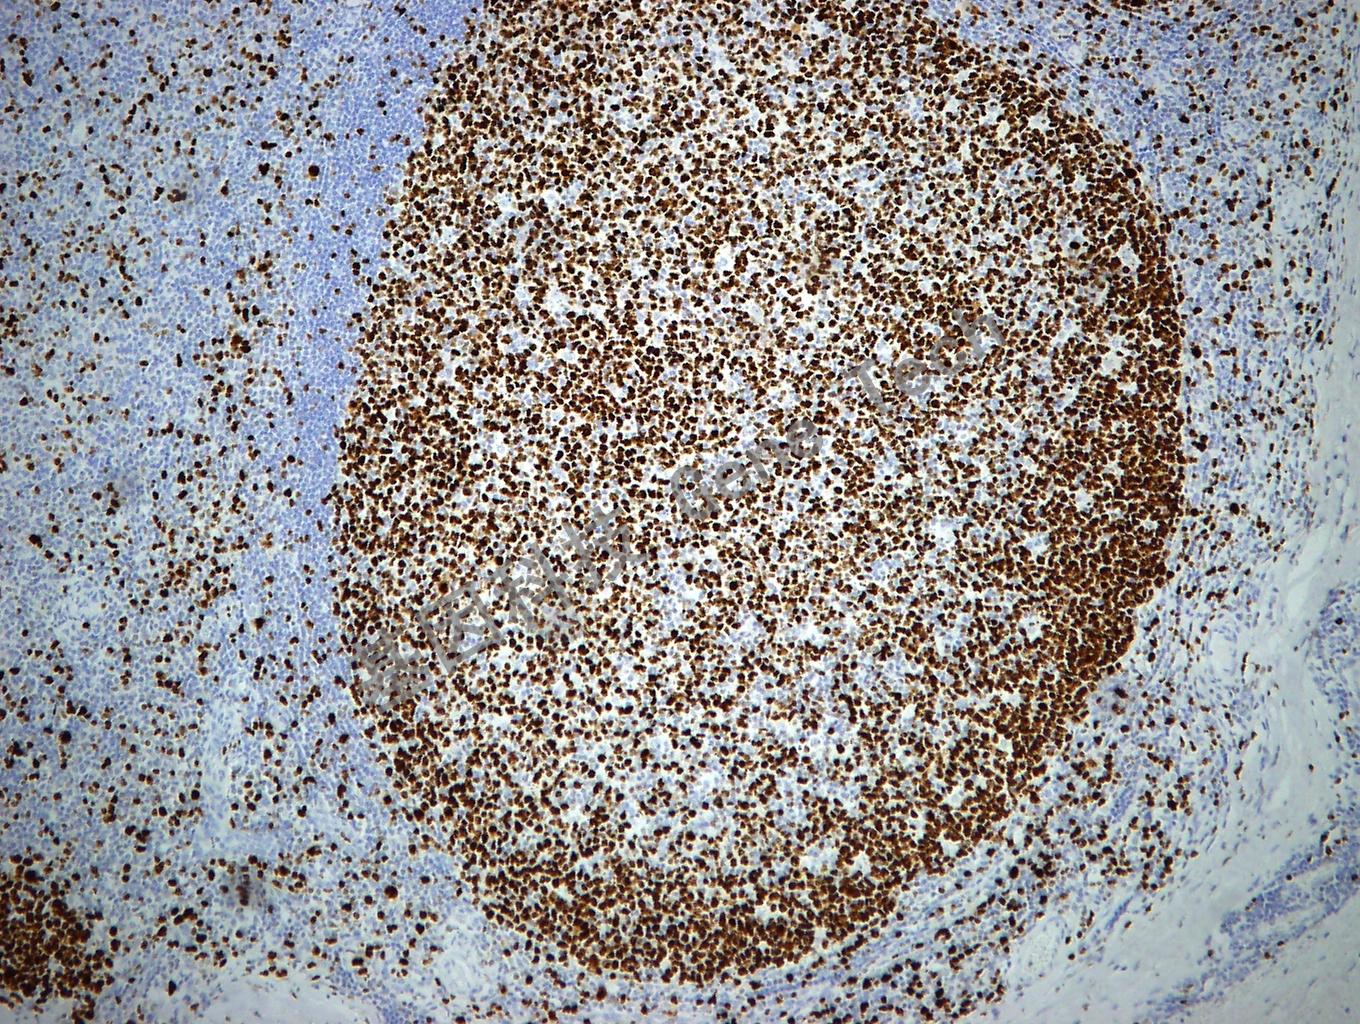

Ki-67 鼠抗人 Ki-67 抗體試劑(免疫組織化學(xué))(GM027)

| 預(yù)處理:高pH熱修復(fù) | 陽性部位:細(xì)胞核 | 陽性對(duì)照:扁桃體 |

| 簡(jiǎn)介:Ki-67可以識(shí)別出在細(xì)胞增殖周期G1、S、G2和M期的細(xì)胞,而處在G0期的細(xì)胞不著色??膳袛嗉?xì)胞的增殖活性,是確定良惡性組織生長(zhǎng)狀態(tài)的標(biāo)記。研究表明,它與乳腺癌的組織學(xué)分型、核分裂指數(shù)和淋巴結(jié)轉(zhuǎn)移情況密切相關(guān),由于Ki-67比PCNA更為直接反應(yīng)細(xì)胞的增殖情況,因此常用于某些惡性腫瘤預(yù)后的一個(gè)重要參考指標(biāo)。有助于判斷淋巴瘤的惡性程度,高級(jí)別淋巴瘤Ki-67一般大于40%或50%。 | ||

| 扁桃體石蠟切片,用 Ki67(GT2094)染色,細(xì)胞核陽性,DAB 顯色。 | ||